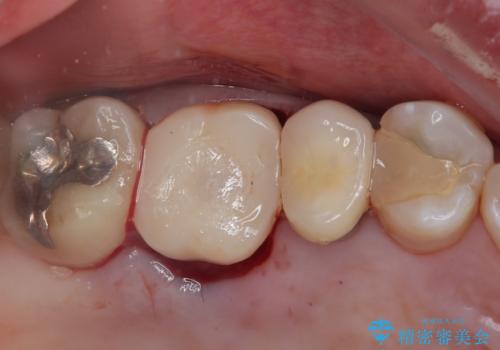

骨量が十分にあることが3次元CTより確認されたため、事前に仮歯を用意した上で、抜歯即時埋入インプラントによる補綴治療を行うこととしました。

来院されるまではインプラント治療を躊躇されていましたが、抜歯即時埋入により、単回の外科処置で治療が終えられることのメリットを理解され、インプラントによる補綴治療を行いました。

スムーズに治療を終えることができました。